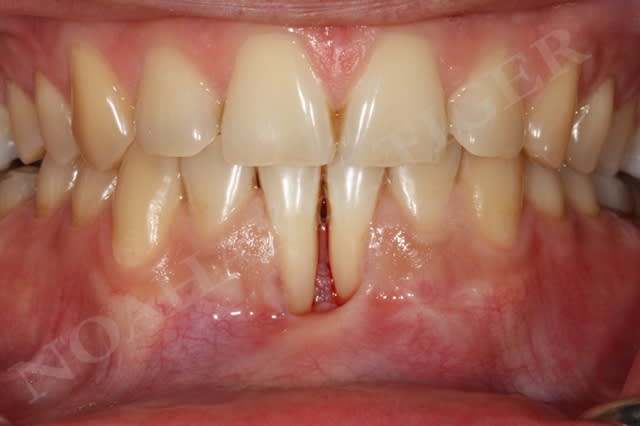

Dans le cas suivant, l'atteinte interproximale 31-41 n'autorise malheureusement aucune solution de recouvrement radiculaire :

Img 8511 llqbsh - Eugenol

En ce qui concerne la mobilité dentaire, c'est une notion que j'ai appris par le biais du cas suivant :

la patiente présente des rétractions gingivales au niveau du bloc incisivo canin inférieur suite à un traitement parodontal initial. Le problème paro de la patiente est sous contrôle et la patiente désire améliorer l'environnement gingival de 33 à 43.

Très bien madame, on y va :